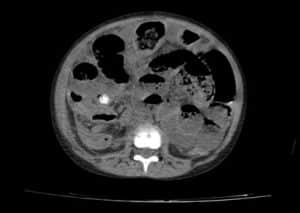

A plain CT of the abdomen was also taken to confirm the diagnosis before being taken to surgery. It showed dilated bowel loops, a radiopaque mass possibly fecalith or appendicolith, and an Inflamed and enlarged appendix. After taking the symptoms, signs, and investigations into consideration, the child was diagnosed with Appendicitis with small bowel obstruction and fecal impaction and taken to surgery. Figures 7 to 9 below show the CT images, axial section of the lower segment of the abdomen.

Figure 7: CT image of axial section of lower segment of abdomen showing dilated bowel loops

Figure 8: CT image showing radiopaque mass, possibly fecalith or appendicolith

Figure 9: CT image showing an inflamed and enlarged appendix with a possible faecolith or appendicolith